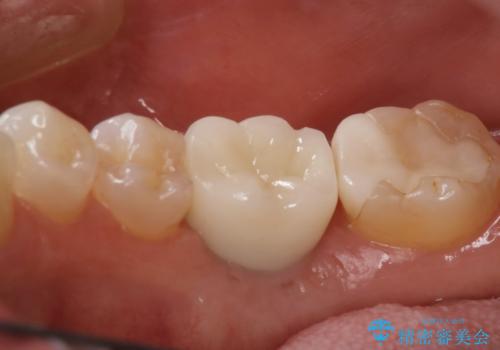

二回の手術を終えて最終的な被せ物が入るまで6〜8ヶ月かかると思います。

歯のなかったところをインプラント治療を行うことによってまた噛める喜びを感じていただけて良かったと思っております。